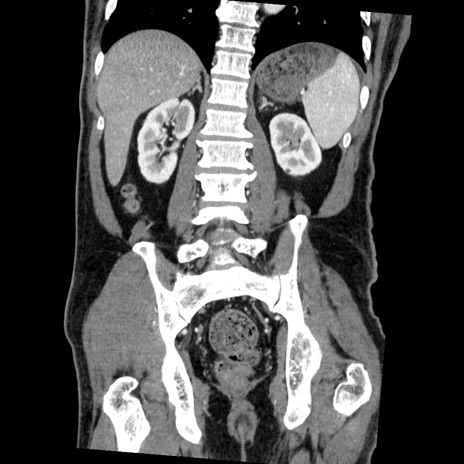

症例22(冠状断像)

【症例】50歳代男性

【主訴】腹痛

【現病歴】AVMからの被殻出血のため回復期リハ病棟入院中。 本日午後3時頃急に下腹部痛が出現した。

【既往歴】AVM、被殻出血、虫垂炎、高血圧

【身体所見】意識晴明、左半身不全麻痺、会話の理解は良好、36.5°C、腹部:膨隆、全体に板状硬、下腹部正中に圧痛点あり、反跳痛-、筋性防御不明、右下腹部にope scar

【データ】WBC 9400、CRP 0.06